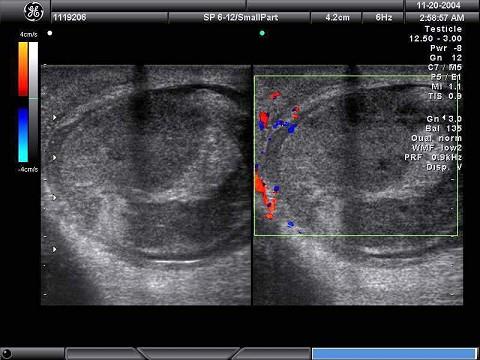

问题 某男,因左阴囊疼痛不适数日,B超检查声像图如下,根据彩色声像图及血流特征,最可能的诊断为?(?)

选项 A.睾丸肿瘤 B.睾丸结核 C.睾丸炎 D.睾丸扭转 E.附睾炎

答案 D